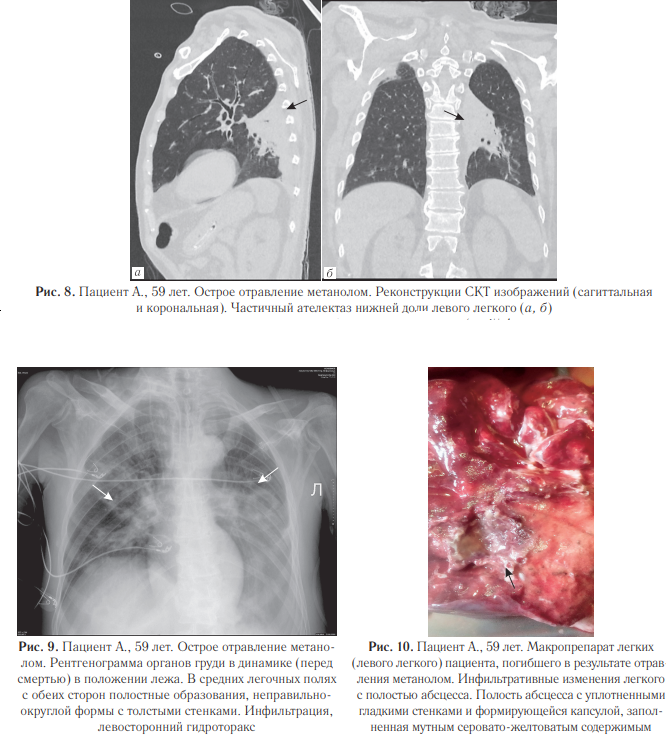

При проведении судебно-медицинской экспертизы выявлены массивные билатеральные гематомы головного мозга (данные аутопсии представлены на рис. 3), а также инфильтративные изменения в легких с полостями абсцессов (рис.10). Исследования легких: при поступлении (рис. 4), рентгенограмма органов грудной полости (рис. 5) и СКТ груди с реконструкциями в динамике через 1 месяц (рис. 6–8).

На рис. 9 представлена рентгенограмма органов грудной полости, выполненная перед смертью пациента. Гистологическая картина по данному случаю отравления. Головной мозг: кровоизлияния (гематомы) с организацией, глиальным рубцом по периферии, с лейкоцитарно-ядерным детритом, слоистым фибрином на фоне эритроцитарных масс; тромбоз некоторых сосудов, кое-где с перифокальным воспалением; фибриноидный некроз стенок отдельных сосудов. Отек головного мозга, местами вплоть до сетчатости, с очагами нейронодистрофии, фокусами выпадения нейронов; прогрессирующий склероз, отек пиальных структур коры головного мозга. Глиальный рубец (в подкорковом отделе), с участками нейронодистрофии, с фокусами кариорексиса, кариолизиса к карнификации; очаговая инфаркт-пневмония (в одном из срезов) с гнойным воспалением, с очагами абсцедирования, местами с признаками организации; полнокровие сосудов с эритро-, лейкостазами, тромбами с фибрином в просветах некоторых сосудов в легких. В сердце: неравномерно-концентрический фиброгиалиноз стенок артериальных сосудов с умеренным сужением просветов отдельных сосудов; периваскулярный, очаговый межуточный сетчатый фиброз; фокусы липоматоза в строме; хаотичное расположение, полиморфизм кардиомиоцитов; фокусы миофрагментации, волнообразной деформации мышечных волокон; неравномерное кровенаполнение сосудов с участками венозно-капиллярной гиперемии.